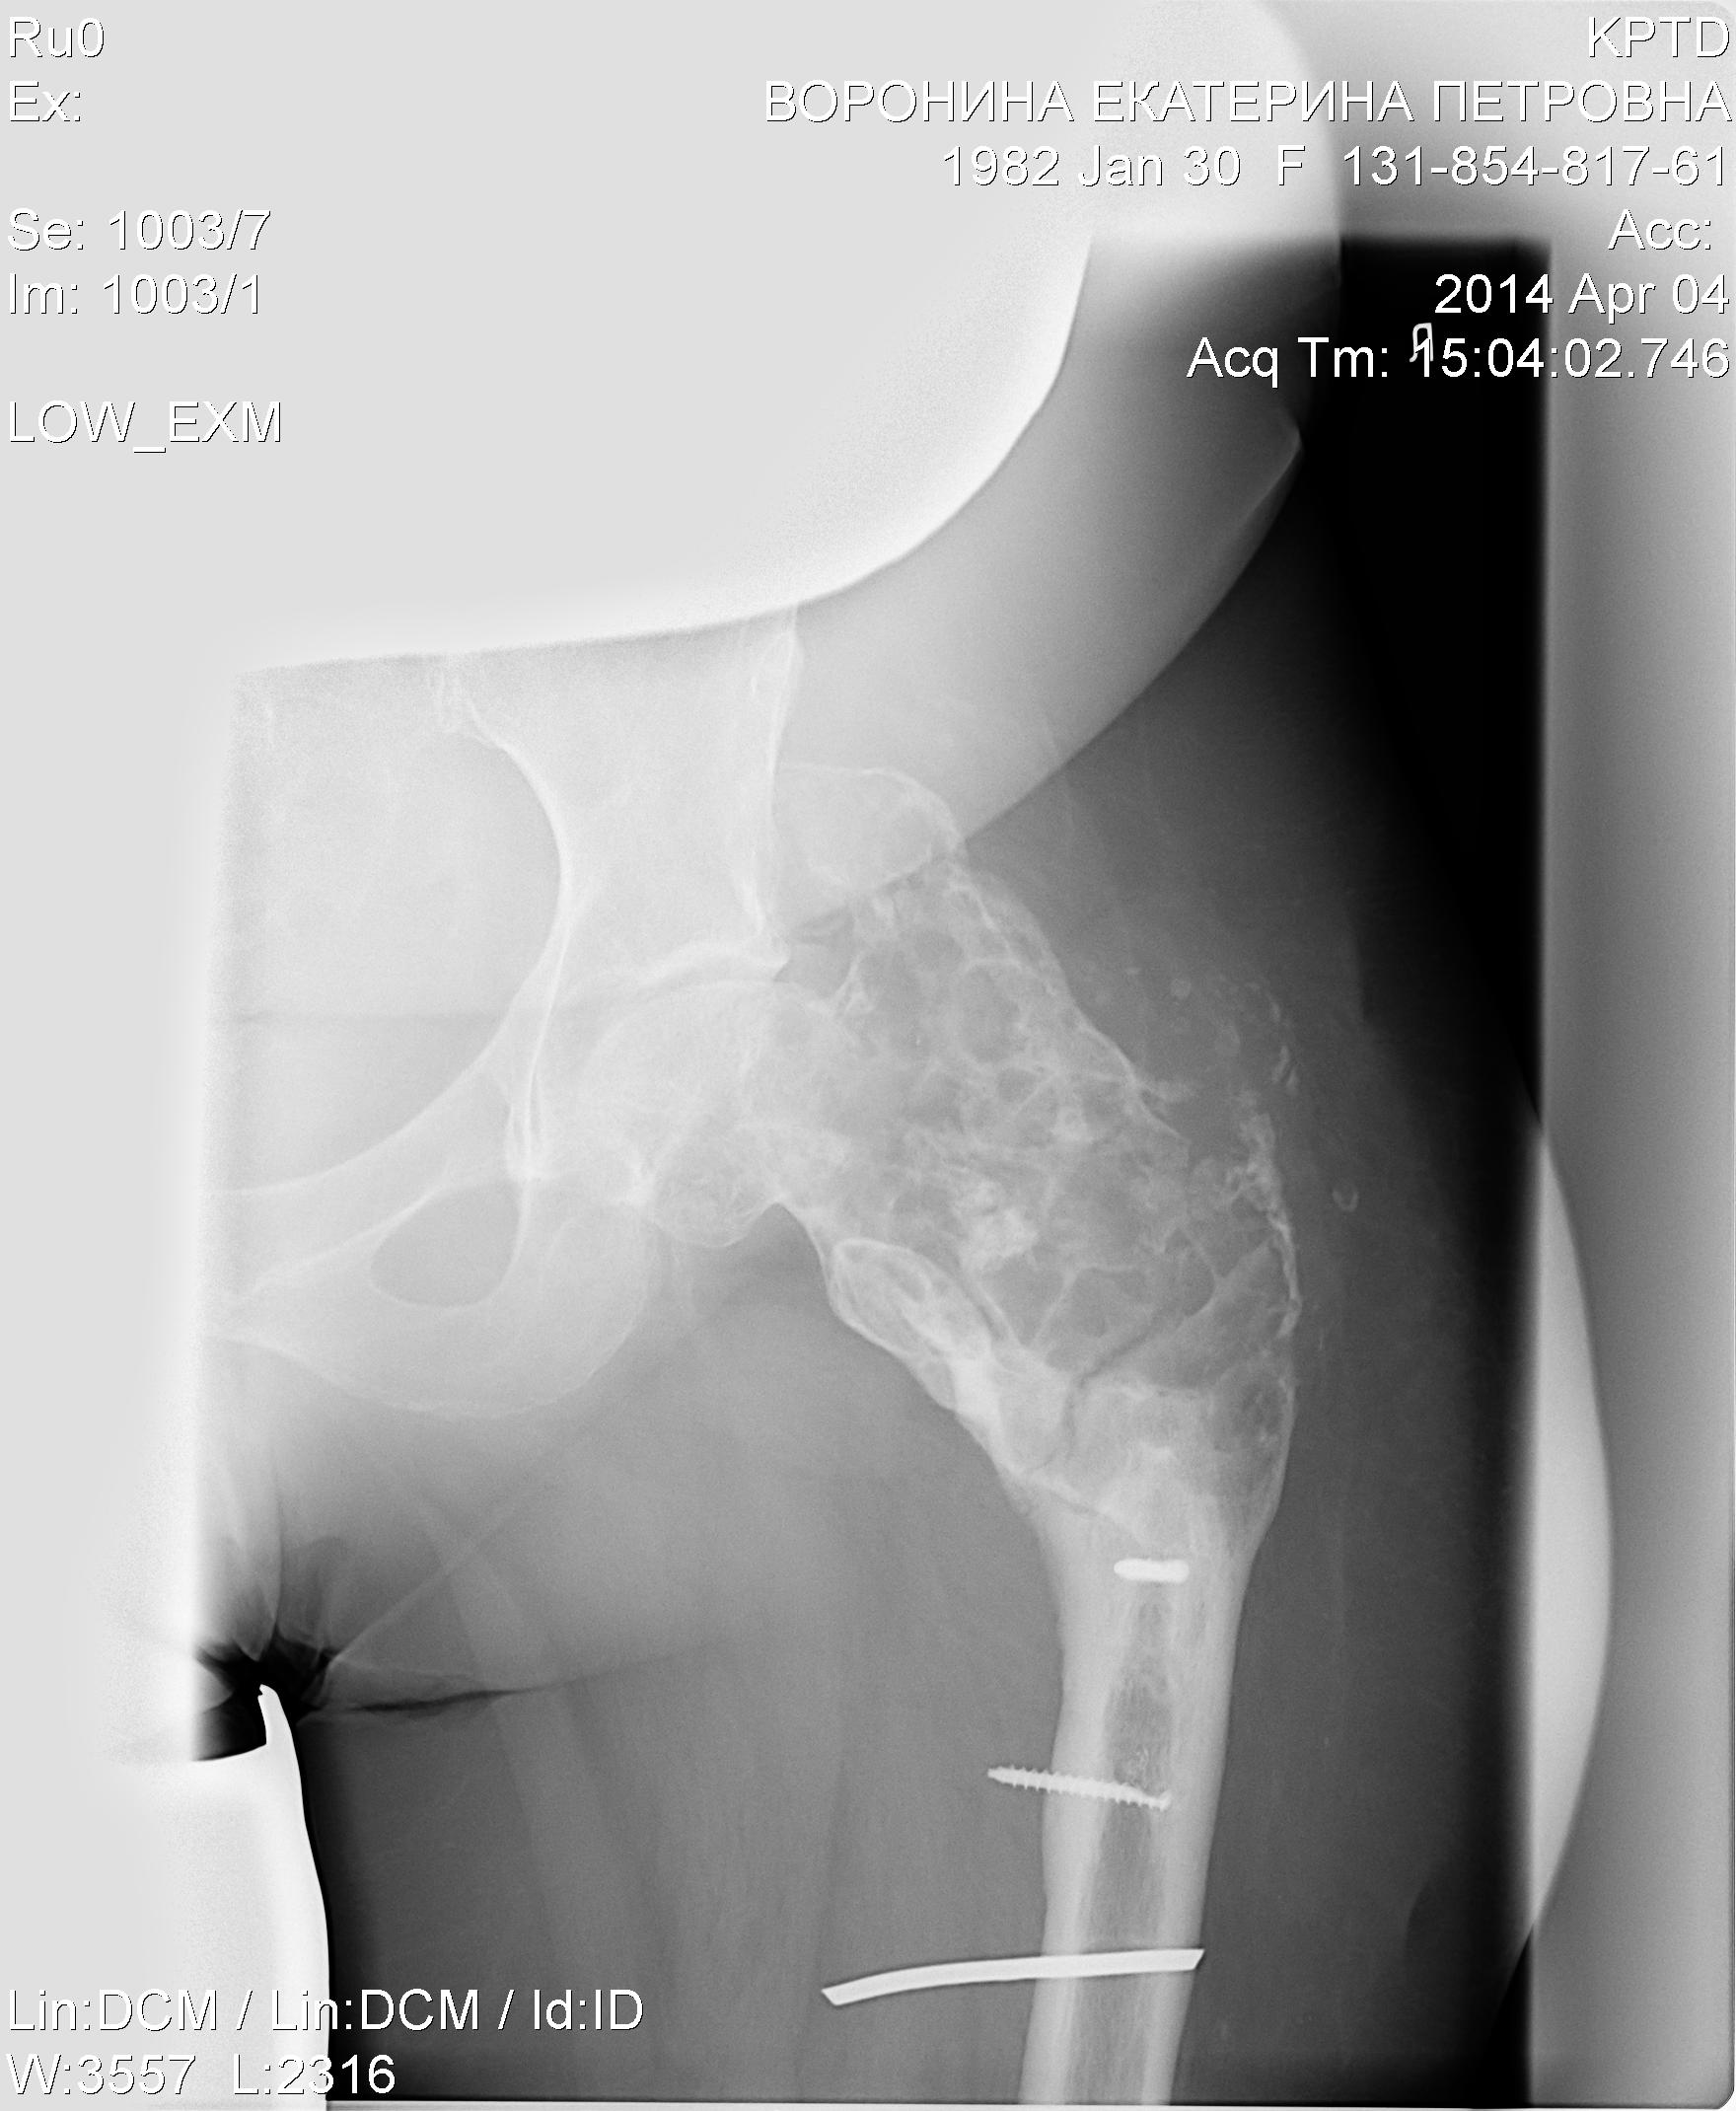

Новые снимки.

КТ в/3 левого бедра по программе 2/2-10/10 с высоким разрешением: Отмечается увеличение в объеме («вздутие») метаэпифиза бедренной кости с истончением, а на отдельных участках с разрушением, замыкательной пластинки, неравномерный склероз диафиза с наличием единичных кистовидных просветлений.Определяется 2 инородных тела в в/3 диафиза – остатки винтов.Мягкие ткани с рубцовыми изменениями. Четких признаков воспалительной инфильтрации не отмечается.Существенной Ro динамики не выявлено.

Заключение: По совокупности данных можно думать о хр. Остеомиелите. Для диф. Диагностики с неопластическим процессом рекомендуется гистологическое исследование.